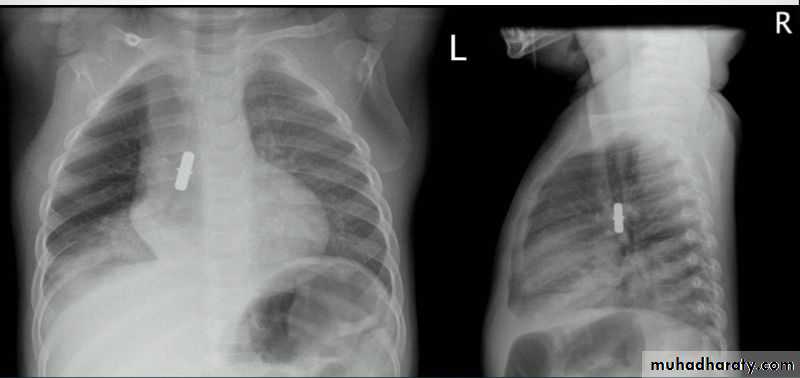

Fall from the 2nd floor

History; too shy to take of his shirt in the pool!

What is the difference?